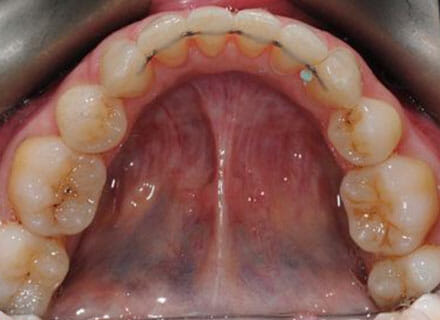

In this case, we needed to reduce the size of the central incisors as they were just too big. This combined with the crowding at the front had caused the lateral incisors to become trapped inside, pushing the big central incisor teeth forwards even more. After reducing the big teeth to a normal size we started with fixed clear bracket brace treatment and were able to complete this case in a little over a year.